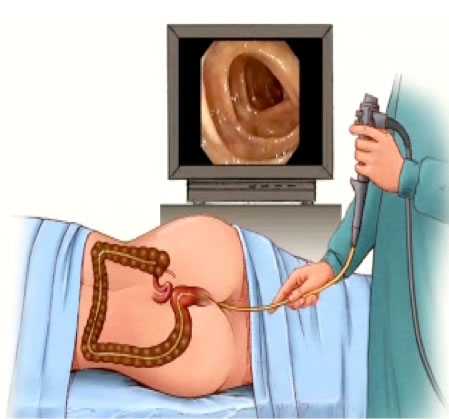

Πολύποδες παχέος εντέρου: Οι πολύποδες είναι νεοπλάσματα, με άλλα λόγια όγκοι που δημιουργούνται από αφύσικο πολλαπλασιασμό κυττάρων στην εσωτερική επιφάνεια, δηλαδή στο βλεννογόνο του παχέος εντέρου. Ο καρκίνος επίσης είναι όγκος που εμφανίζεται με ανάλογο τρόπο, όμως στον καρκίνο τα κύτταρα είναι πιο επιθετικά, έχουν διηθήσει το τοίχωμα του εντέρου πιο πέρα από το βλεννογόνο, αλλά και έχουν την ιδιότητα να δημιουργούν μεταστάσεις. Έτσι οι απλοί πολύποδες, επειδή έχουν καλύτερη βιολογική συμπεριφορά, ονομάζονται καλοήθη νεοπλάσματα, ενώ οι καρκίνοι είναι τα κακοήθη νεοπλάσματα του παχέος εντέρου. Η αλήθεια είναι ότι η πλειοψηφία των καρκίνων του παχέος εντέρου δημιουργούνται από πολύποδες. Βέβαια όλοι οι πολύποδες δεν αλλάζουν και γίνονται καρκίνοι. Επειδή όμως δεν γνωρίζουμε ποιοι πολύποδες θα γίνουν τελικά καρκίνοι, είναι καλό να τους ανιχνεύουμε όσο πιο νωρίς γίνεται και να τους αφαιρούμε πριν γίνουν καρκίνοι. Για να γίνει αυτό με επιτυχία, ο καλύτερος τρόπος είναι η κολονοσκόπηση, δηλαδή αυτή η ειδική εξέταση με την οποία εξετάζεται η εσωτερική επένδυση του παχέος εντέρου και εάν βρεθούν πολύποδες αφαιρούνται την ίδια στιγμή με τη βοήθεια ενός ειδικού εργαλείου, που λέγεται ενδοσκοπικός βρόγχος. Όπως και ο καρκίνος, οι πολύποδες του παχέος εντέρου εμφανίζονται κυρίως σε ανθρώπους ηλικίας άω των 50 ετών. Η πρώϊμη ανεύρεσή τους και η αφαίρεση τους, πριν μετατραπούν σε καρκίνο, με τη βοήθεια της κολονοσκόπησης στην οποία πρέπει να υποβάλλονται οι άνθρωποι στα 50 χρόνια της ζωής τους, είναι ο αποτελεσματικότερος τρόπος πρόληψης και ελάττωσης του κινδύνου προσβολής από καρκίνο παχέος εντέρου.

Η κολονοσκοπική αφαίρεση των πολυπόδων προλαμβάνει τον καρκίνο του παχέος εντέρου

Ο καρκίνος του παχέος εντέρου ΜΠΟΡΕΙ ΝΑ ΠΡΟΛΗΦΘΕΙ. Σχεδόν όλοι οι καρκίνοι του παχέος εντέρου οφείλονται σε πολύποδες, οι οποίοι είναι αρχικά καλοήθεις. Ο εντοπσμός και η αφαίρεση αυτών των πολυπόδων με κολονοσκόπηση μειώνει τον κίνδυνο εμφάνισης καρκίνου του παχέος εντέρου. Ο γιατρός σας μπορεί να παρέχει ακριβείς συστάσεις για τον προσυμπτωματικό έλεγχο του καρκίνου του παχέος εντέρου βάσει του ατομικού και οικογενειακού ιστορικού σας.

Ο προληπτικός έλεγχος με κολονοσκόπηση ξεκινά στην ηλικία των 50 ετών σε ασθενείς με μέσο κίνδυνο, ή σε μικρότερες ηλικίες σε ασθενείς που διατρέχουν υψηλότερο κίνδυνο να αναπτύξουν καρκίνο του παχέος εντέρου. Έτσι ασθενείς που έχουν οικογενειακό ιστορικό καρκίνου παχέος εντέρου, δηλαδή συγγενή ή συγγενείς πρώτου βαθμού με καρκίνο, πρέπει να ξεκινούν τον έλεγχο με κολονοσκόπηση στα 40 τους χρόνια ή σε ηλικία 10 ετών πριν από την ηλικία εμφάνισης του καρκίνου στο συγγενή. Για παράδειγμα, εάν ο πατέρας ενός ανθρώπου διαγνώστηκε με καρκίνο στα 45 του, τότε ο γιος πρέπει να ξεκινήσει τις τακτικές κολονοσκοπήσεις στην ηλικία των 35 ετών.

Η κολονοσκόπηση

Αν και η κολοσκόπηση αποτελεί το καλύτερο μέσο προληπτικού και προσυμπτωματικού ελέγχου για τον καρκίνο του παχέος εντέρου, υπάρχουν διαθέσιμες και άλλες λιγότερο ακριβείς εξετάσεις, όπως η ανίχνευση μικροσκοπικής απώλειας αίματος στα κόπρανα, η ανίχνευση DNA στα κόπρανα, η εύκαμπτη ορθοσιγμοειδοσκόπηση, ο βαριούχος υποκλυσμός και η πλέον σύγχρονη, αλλά όχι και πάντα διαθέσιμη σε πολλά συστήματα δημόσιας υγείας, αξονική κολονογραφία ή εικονική κολονοσκόπηση. Εάν σε κάποια από αυτές τις δοκιμασία βρεθεί κάτι ύποπτο, στον ασθενή πρέπει σαφώς να συσταθεί κολονοσκόπηση.

Η υποψία για την ύπαρξη καρκίνου στο παχύ έντερο τίθεται από τα συμπτώματα του ασθενούς. Μετά την επίσκεψη του ασθενούς στο γιατρό, αυτός πρέπει να προβεί στη λήψη πλήρους ιστορικού και στη διενέργεια της απαραίτητης αντικειμενικής εξέτασης. Κατά την εξέταση του ασθενούς περιλαμβάνεται και η δακτυλική εξέταση του πρωκτού, κατά την οποία μπορεί να αποκαλυφθεί καρκίνος που προσβάλλει το τελικό τμήμα του παχέος εντέρου, δηλαδή το ορθό. Στη συνέχεια ο ασθενής πρέπει να υποβληθεί σε κολονοσκόπηση, η οποία αποτελεί την πιο συχνή διαγνωστική εξέταση για την ανακάλυψη του καρκίνου του παχέος εντέρου. Άλλες εξετάσεις μπορεί να είναι ενδεικτικές ύπαρξης καρκίνου, αλλά η κολονοσκόπηση είναι η πλέον επιβεβαιωτική μέθοδος. Εάν κατά την κολονοσκόπηση αποκαλυφθεί κάποια ανώμαλη, μη φυσιολογική περιοχή ή αλλοίωση πάνω στο βλεννογόνο του παχέος εντέρου, όπως ένας πολύποδας, μία μάζα, ένα μόρφωμα ή ένας όγκος που προβάλλει από το έντερο μέσα στον αυλό του, τότε, εφόσον ο πολύποδας μπορεί να αφαιρεθεί με τον ειδικό ενδοσκοπικό βρόγχο, αυτός αφαιρείται εξολοκλήρου. Ειδάλλως λαμβάνεται ένα μικρό τμήμα του μορφώματος ή του όγκου με τη βοήθεια μιας λαβίδας βιοψίας. Τόσο ο πολύποδας όσο και το παθολογικό τμήμα πρέπει να σταλούν για βιοψία, δηλαδή πρέπει να γίνει μικροσκοπική εξέτασή τους για να αναζητηθούν καρκινικά κύτταρα. Εάν ο παθολογοανατόμος που εξετάζει τα παρασκευάσματα κάτω από το μικροσκόπιο βρει καρκινικά κύττρα, τότε τίθετια και η διάγνωση του καρκίνου του παχέος εντέρου.

Ένα άλλο κοινό σενάριο για τη διάγνωση του καρκίνου του παχέος εντέρου είναι αυτό στο οποίο ένα άτομο κατά τα άλλα υγειές προσέρχεται για κολονοσκόπηση στα πλαίσια προσυμπτωματικού ελέγχου. Αν και τις περισσότερες φορές σε κολονοσκοπήσεις που γίνονται στα πλαίσια του προληπτικού ελέγχου αποκαλύπτονται μόνο καλοήθεις πολύποδες, δεν είναι απίθανο να βρεθεί και καρκίνος, ο οποίος συνήθως βρίσκεται σε σχετικά αρχικό στάδιο. Στον ασυμπτωματικό ασθενή που υποβάλλεται σε προληπτική κολονοσκόπηση είναι εφικτή η έγκαιρη και πρώϊμη διάγνωση του καρκίνου, γεγονός που κάνει και τη θεραπεία της νόσου αυτής πιο εύκολή αλλά και πιο επιτυχημένη και αποτελεσματική. Πάντως πρέπει να τονιστεί ότι δεν υπάρχει καμία εξέταση αίματος που να θέτει τη διάγνωση του καρκίνου του παχέος εντέρου.